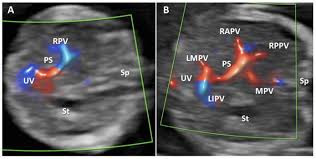

복부 초음파는 간, 담낭, 췌장, 비장, 신장, 방광, 복부 대혈관 등 주요 장기를 대상으로 시행됩니다.

간은 복부 초음파의 핵심 관찰 대상입니다. 간 실질의 에코 패턴을 통해 지방간 여부를 비교적 정확하게 판단할 수 있으며, 지방 침착의 정도에 따라 경증, 중등도, 중증으로 나누어 추정이 가능합니다. 또한 간낭종, 간혈관종과 같은 양성 종양은 초음파에서 특징적인 모양으로 관찰되는 경우가 많아 추적 관찰 여부를 결정하는 데 도움이 됩니다. 간경변이 진행된 경우에는 간 표면이 불규칙해지고 비장이 커지는 소견이 함께 나타날 수 있으며, 이는 만성 간질환의 중요한 단서가 됩니다. 다만 간암의 경우 초기 병변은 초음파에서 놓칠 수 있어, 고위험군에서는 CT나 MRI와 병행하는 것이 일반적입니다.

담낭 결석은 복부 초음파로 가장 쉽게 진단되는 질환 중 하나입니다. 작은 결석이라도 초음파에서는 후방 음영을 동반한 고에코 병변으로 비교적 명확하게 보입니다. 담낭 용종 역시 크기와 형태를 파악하여 추적 관찰 또는 추가 검사의 기준을 정할 수 있습니다. 담낭염이 있는 경우 담낭벽 비후, 담낭 주변 액체 저류 등의 소견이 동반될 수 있으며, 이는 급성 복통의 원인을 설명하는 중요한 정보가 됩니다. 담도 확장 여부를 확인함으로써 담도 결석이나 담도 폐쇄 가능성도 간접적으로 추정할 수 있습니다.